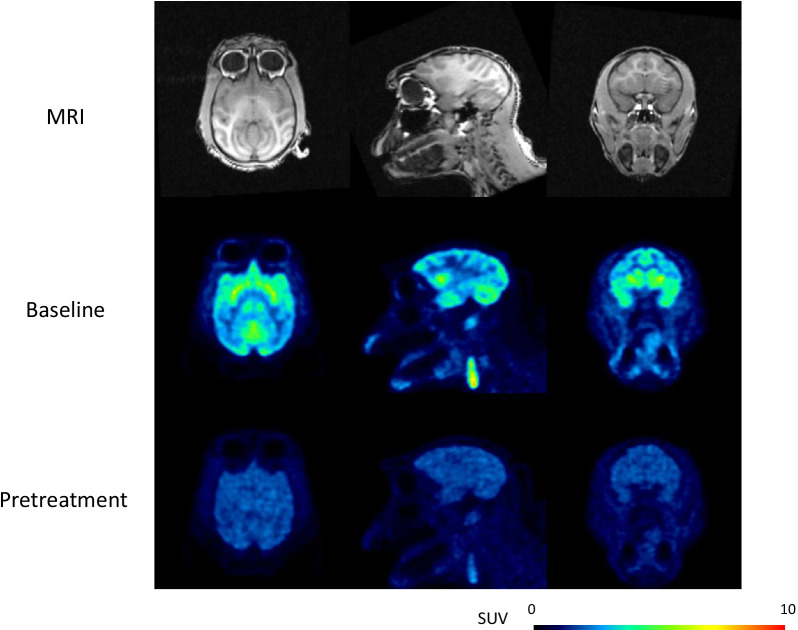

The injected radioactivity (n = 20) of [11C]PF-06809247 was 146 ± 10 (mean ± SD) (range; 120–162) MBq. The molar radioactivity at the time of injection was 1510 ± 963 (392–4388) GBq/µmol, and the injected mass was 0.06 ± 0.04 (0.01–0.15) µg. Retention of brain uptake was clearly decreased after pretreatment of PF-06818883 (NHP4; 0.42 mg/kg, Fig. 1). TACs for several brain regions demonstrated decreased radioactivity, which corresponded to PET images (NHP4; 0.42 mg/kg, Fig. 2a, b, Additional file 1: Figure S1).

In this study, we present a novel MAGL PET radioligand, [11C]PF-06809247 which showed high uptake in the NHP brain and clear blocking effect by a selective MAGL inhibitor. The uptake of [11C]PF-06809247 was relativley uniform thoughout the brain with slightly higher uptake in the celleberum and putamen and lower uptake in the cerebral cortical regions. The distribution was relatively similar as MAGL mRNA expression in the rat brain previously reported [ref. 16]. Brain uptake was clearly decreased in all brain regions following pretreatment with a high dose of a previously described selective MAGL inhibitor. The relationship between plasma concentration and occupancy was observed in a dose-dependent manner. This suggests that [11C]PF-06809247 is sensitive enough to detect a range of MAGL inhibition and demonstrates the ammenability of [11C]PF-06809247 for assessing MAGL occupancy in vivo.